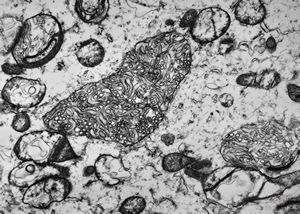

phagocytosed Nocardia (Actinomycetales) … cerebellar absces